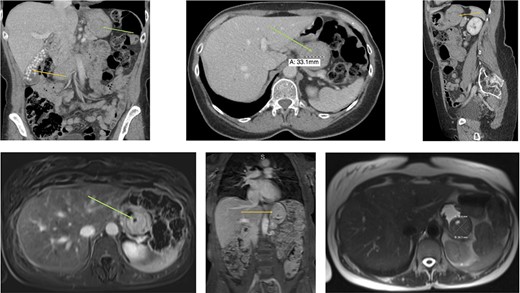

Radiology (a) CT scan coronal view showing the gallbladder filled with radiolucent stones (orange arrow) and the GIST in the stomach (green arrow). (b) CT scan axial view showing the gastric GIST in the submucosal tissue (green arrow). (c) CT scan sagittal view showing the gastric GIST on the posterior wall of the stomach (orange arrow). (d) MRI axial view showing the tumour with a pneumatocele (green arrow). (e) MRI coronal view showing the tumour on the posterior wall of the stomach (orange arrow) with the visible pneumatocele. (f) T2 weighted MRI axial view showing the GIST dimensions.

An abdominal examination revealed no palpable lesions or abdominal wall hernia. She had no clinical signs of an acute abdomen. Her medical history was significant for asthma, dermatomycosis and endometriosis. Radiological imaging, with an abdominal ultrasound confirmed cholelithiasis but no cholecystitis or choledocholithiasis. The ultrasound also showed an incidental gastric lesion in the posterior wall of the stomach. A subsequent computerized tomography (CT) scan showed an isolated lesion in the posterior wall of the stomach and no obvious gastric lymphadenopathy (Fig. 1a–c). Radiolucent gallstones were also visualized on the CT scan (Fig. 1a). Differential diagnosis of the gastric lesion included a leiomyoma or a GIST. Upon discussion with an interventional radiologist, the gastric lesion was deemed radiologically inaccessible to percutaneous biopsy. A magnetic resonance imaging (MRI) scan was performed to confirm the diagnosis. MRI showed a well-circumscribed soft tissue lesion in the posterior wall of the stomach in keeping with a gastric GIST (Fig. 1d–f).